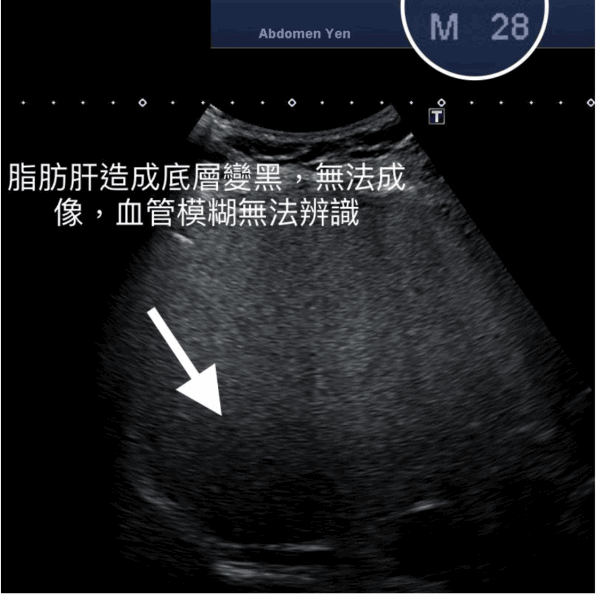

台湾胃肠肝胆科医生钱政弘在其facebook专页分享一张肝脏超声波照片指,该名老翁日前到医院进行例行检查,结果显示其肝脏情况一切正常,没有脂肪肝和纤维化的迹象。钱医生又分享另一张28岁年轻人的超声波照片,指出该名年轻人患有脂肪肝,照片底层的肝脏因为有脂肪肝,令影像变黑无法辨认。相比之下,老翁的超声波照片更清晰,肝脏纹理细致,反而比28岁患者更健康。

▲28岁患者的超声波照片